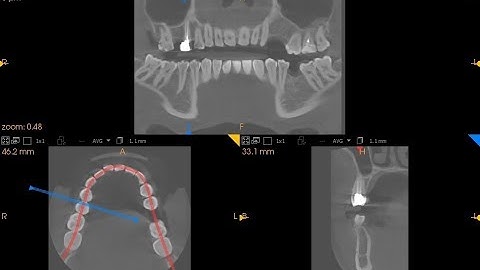

CBCT to Surgical Guide Training Video - Using the Impression Inversion Protocol